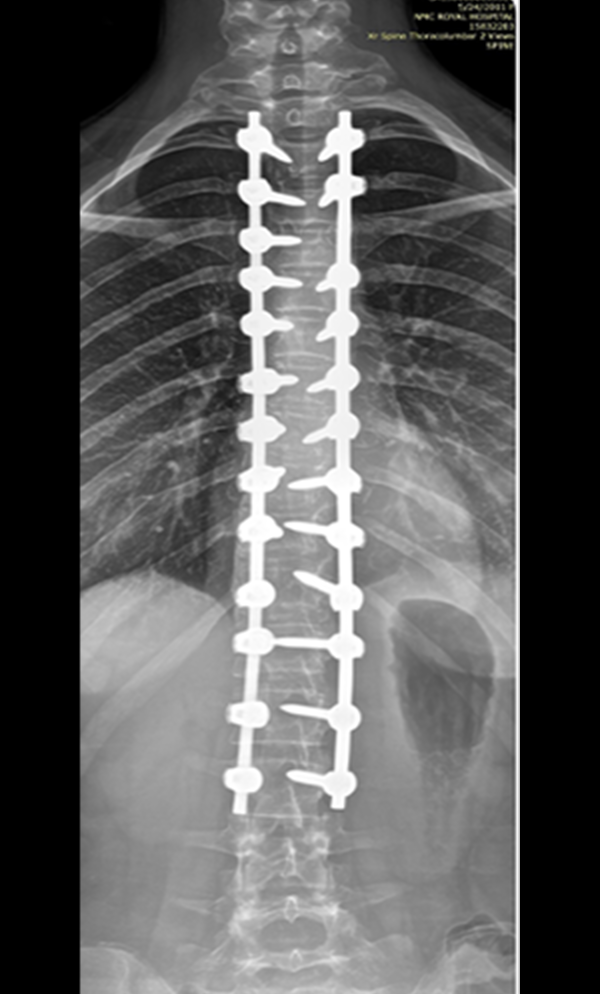

The procedure involves repositioning the spine and securing it with Screws and Rods. Bone graft is then placed so the treated vertebrae gradually heal together into one solid segment. This creates long-term stability, preventing further curve progression and improving overall alignment.

The surgical procedure typically involves Long-Segment Stabilization using Screws and Rods, and may also include Pelvic Fixation. The goal of the surgery is to improve overall alignment, sitting balance, and long-term care needs. Due to the medical complexities of these patients, a Multidisciplinary Approach is essential in planning the surgical intervention.

Gallery : Before - After

After

Before